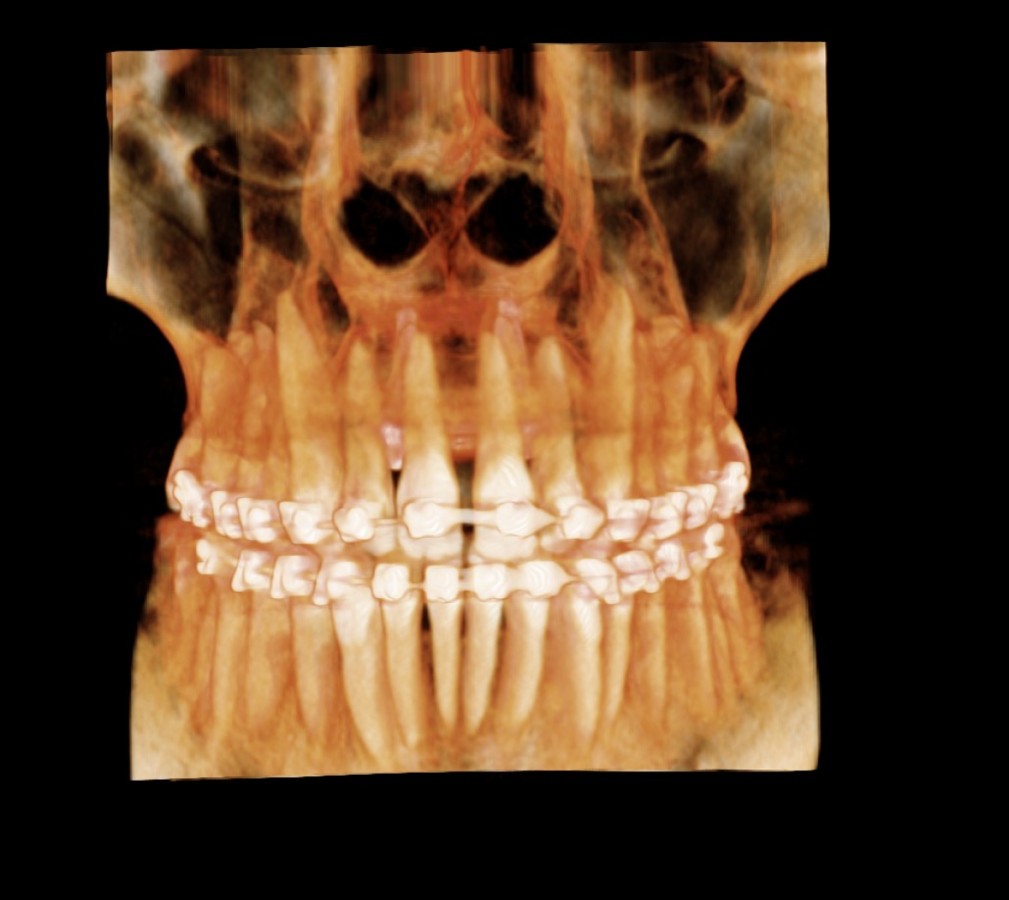

Przekój szczęki przed leczeniem

Pacjent przede leczeniem obecny zgryz krzyżowy, stłoczenia.